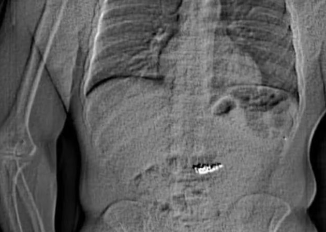

Homem acusado de roubo engoliu as evidências pouco antes de ser preso; caso se deu em Orlando, no estado da Flórida. Por Tatiane Martinelli | GNEWSUSA […]